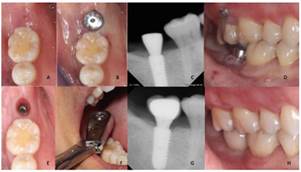

La paciente acudió a consulta de revisión cada 2 semanas. Se aplicó una fuerza de 150g. en el segundo molar superior derecho con una cadena ortodóntica cada 2 semanas eliminando un eslabón de esta misma durante 6 meses como lo escribe Kravitz y Carrillo4,6. Después de 5 meses postquirúrgicos, se descubrió el implante y se colocó el tornillo de segunda fase (5mm x 5mm) y fue retirado el botón oclusal del 1.7. Se colocó una corona atornillada sobre implante y se retiraron mini-implantes (Fig. 5).

Al finalizar el tratamiento se logró la intrusión de 4mm del segundo molar superior derecho sin complicaciones en el diente adyacente en 4 meses y la sustitución del espacio ausente del segundo molar inferior derecho por un implante dental. La paciente no refirió sintomatología de la ATM. Se le hizo hincapié sobre la importancia de continuar con su fase de mantenimiento cada 3 meses para asegurar salud periimplantaria y periodontal.